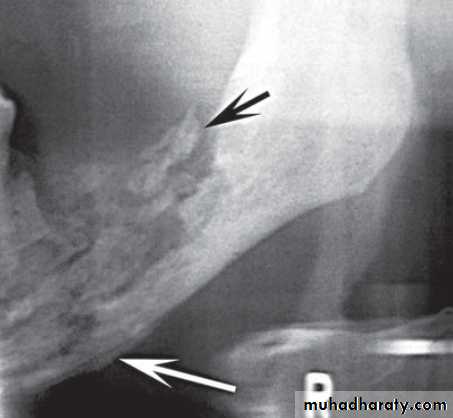

Extraction of /6, showing the typical destructive appearance (solid arrow),

resulting in a pathological fracture (open arrow). Radiotherapy had been given several years previously

( A and B ) of the same patient taken 1 year apart demonstrate a developing sclerotic bone pattern with a sequestra (arrow) related to bisphosphonate therapy.